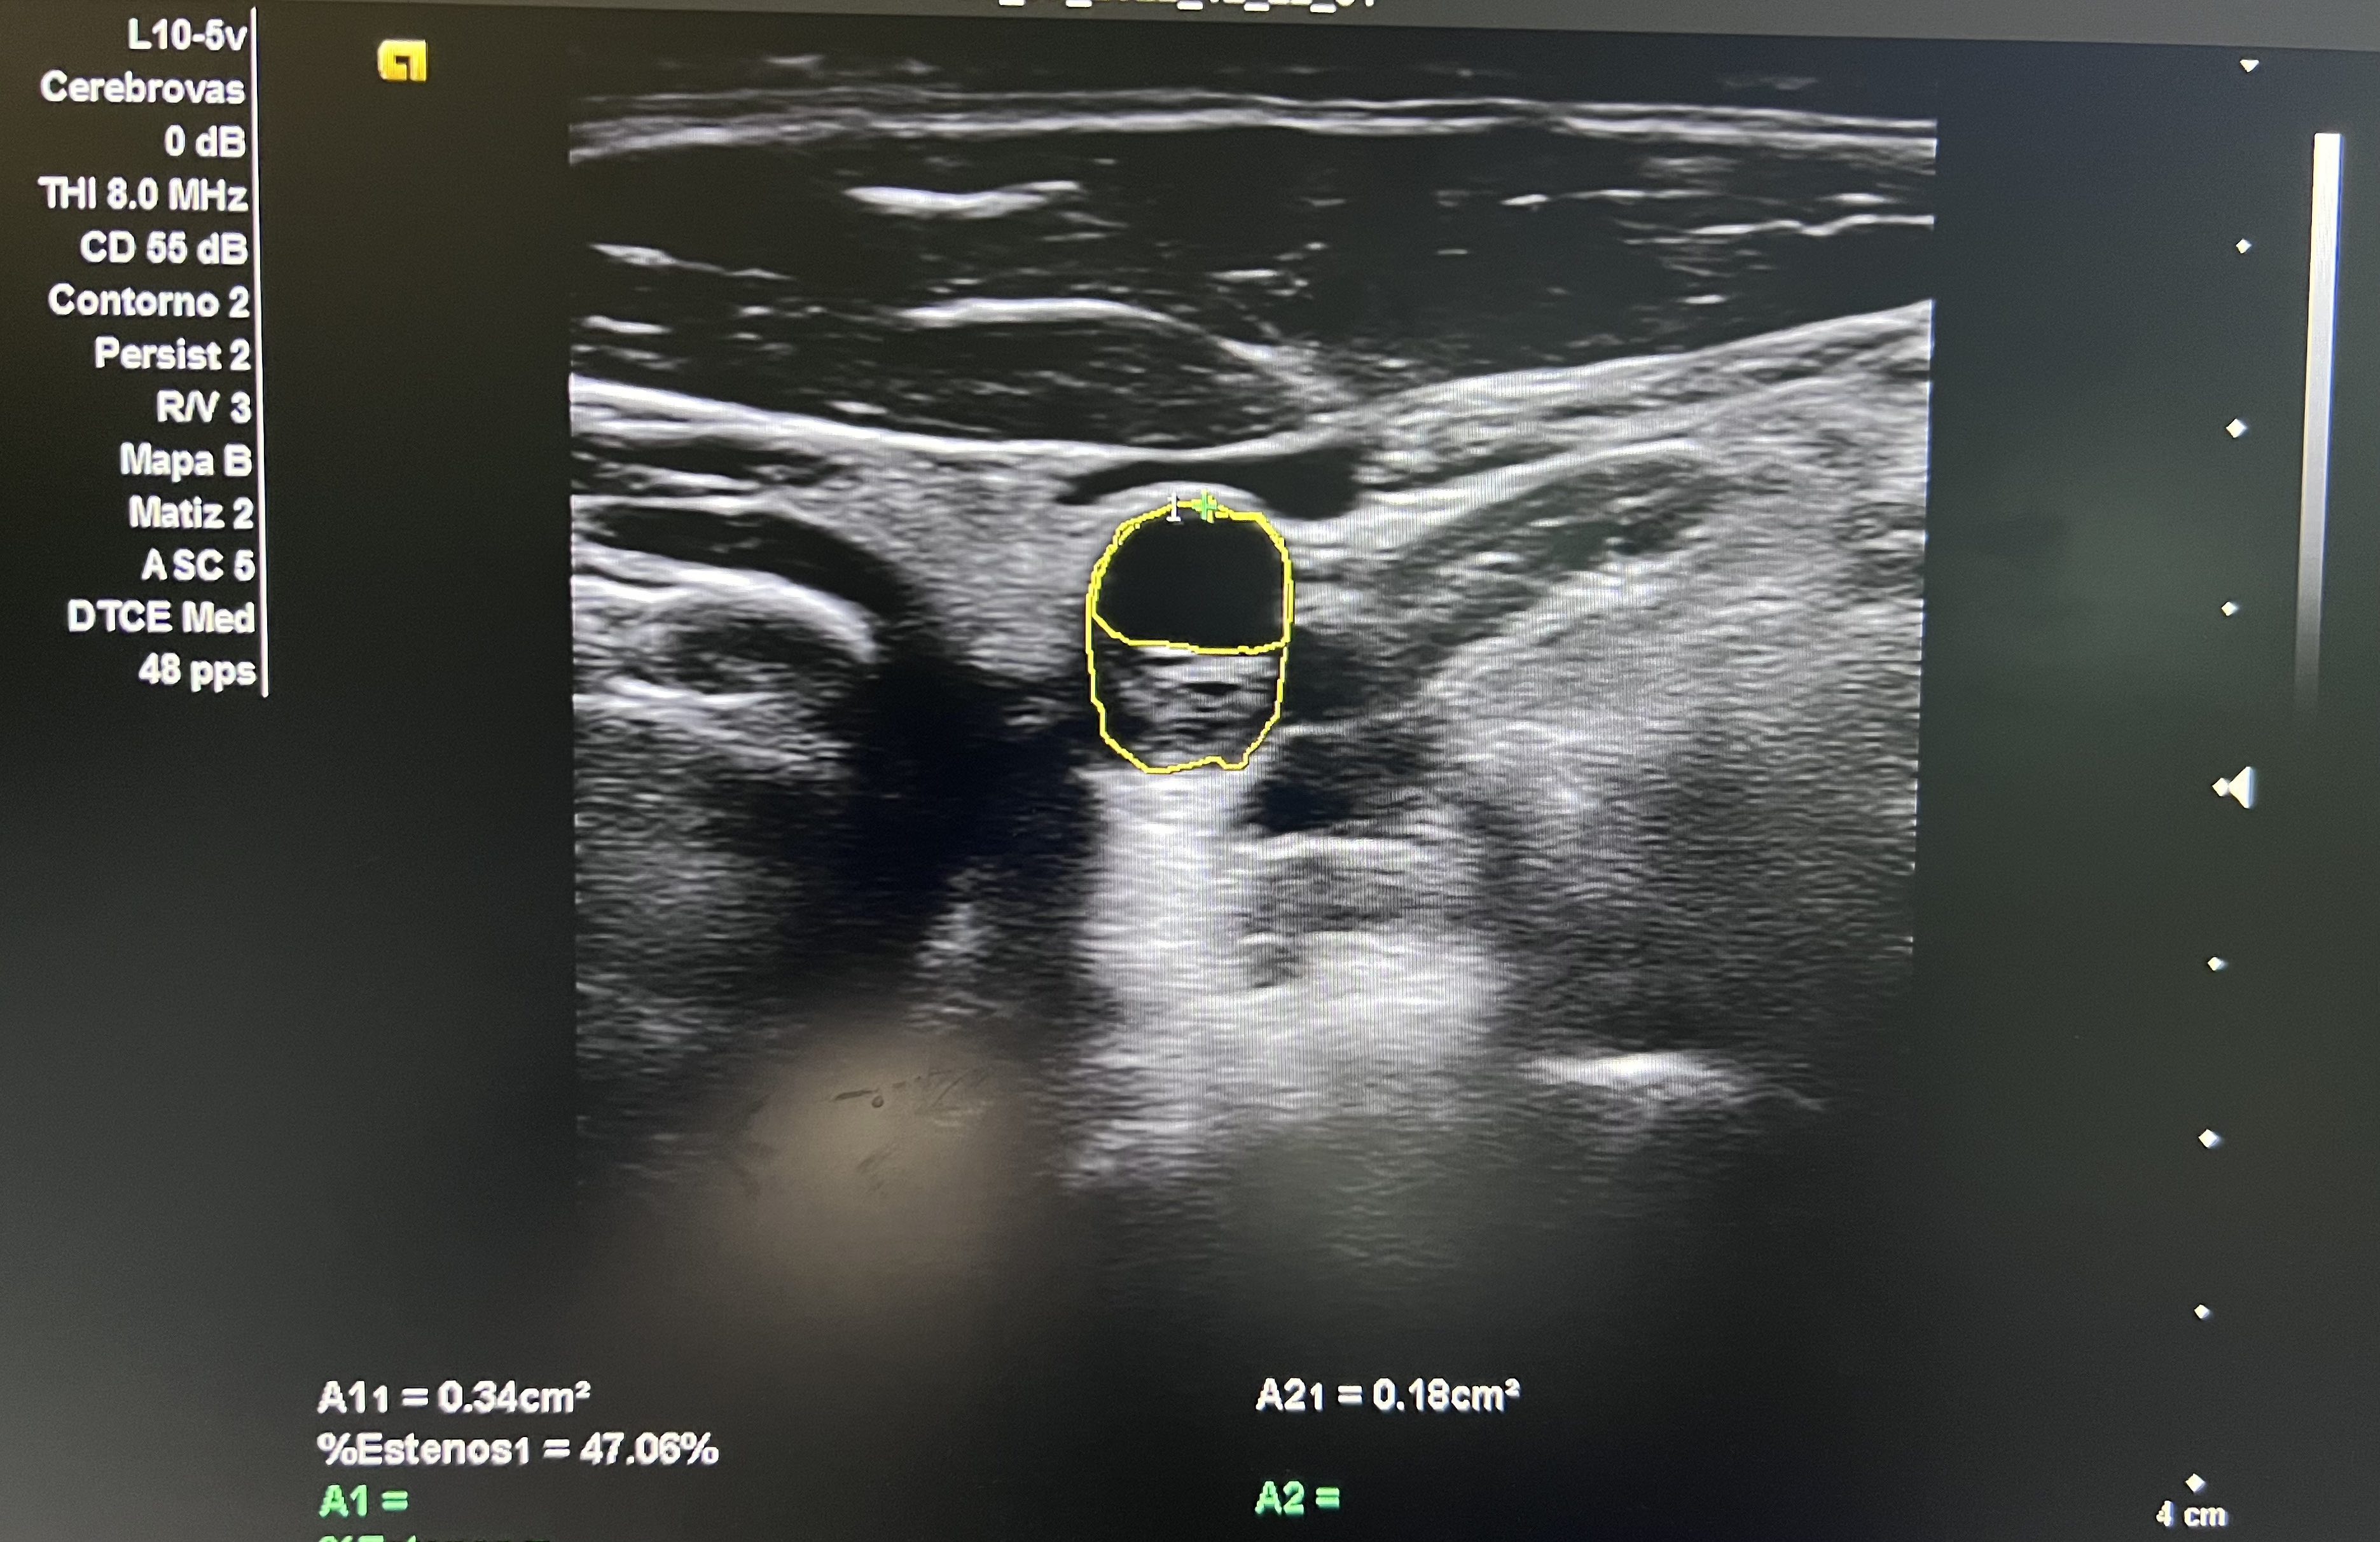

Hallazgos ecográficos

Aorta abdominal de calibre normal. Arteria carótida derecha sin lesiones. En arteria carótida común izquierda se observa placa longitudinal desde porción media hasta proximal que obstruye un 58% en su diámetro máximo.